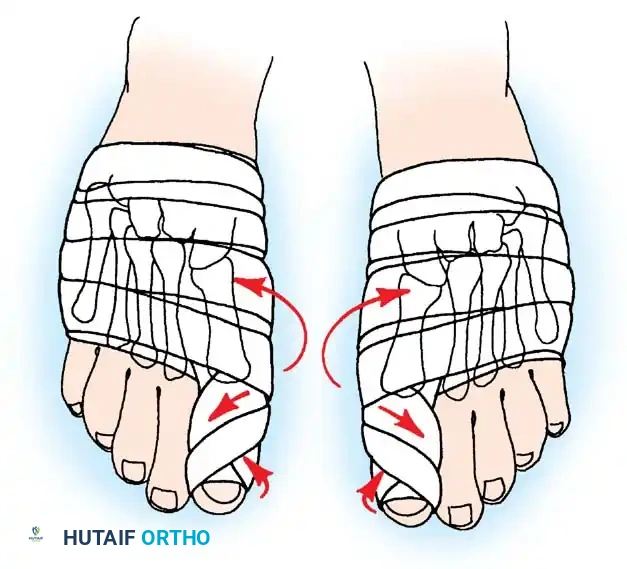

AFTERTREATMENT A bulky compression dressing is applied to the forefoot, and the foot is placed in a position of maximal elevation for 48 to 72 hours. Bathroom privileges only are allowed, and the patient must wear a woodensoled shoe. Increased ambulation after 72 hours is allowed as tolerated by the patient. The need for crutches or a walker varies, but assisted ambulation is not encouraged unless the patient is unsteady. At 3 weeks, if the wounds are healed, the sutures are removed, and adhesive strips are applied if needed; leaving the sutures in longer has no untoward effect. Some type of immobilizer or toe spacer to hold the toe in proper alignment is used (Fig. 78-25). The wooden-soled shoe is used for 3 to 4 weeks, at which time a deep shoe with a wide toe box is recommended; a jogging shoe is suffi cient; an extra-depth orthopaedic shoe with a soft toe box also is permissible. The toe spacer is worn for 6 weeks. At 12 to 14 weeks, a reasonably attractive shoe usually can be worn. The period of postoperative edema varies, however, and it may take 4 to 6 months before this type of shoe is tolerated. This is explained to the patient before surgery. DuVries and Mann made major modifi cations in the McBride bunionectomy, including the following:

Weekly postoperative dressing changes for 6 to 8 weeks are emphasized (Fig. 78-26E), followed by use of a night splint that holds the hallux in position until the end of the third month (Fig. 78-27). Mann recommended using the McBride procedure alone in only 10% to 15% of patients undergoing hallux valgus correction. The decision is made intraoperatively by checking reduction of the intermetatarsal angle with manual lateral displacement of the fi rst metatarsal. If the reduction is secure, no proximal metatarsal osteotomy is necessary. In the remaining patients, proximal crescentic fi rst metatarsal osteotomy is done in addition to the distal soft-tissue realignment.